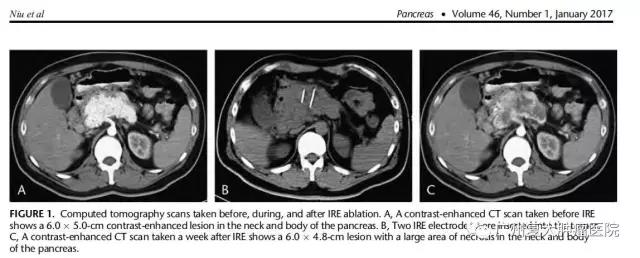

这是一例非常罕见的癌种。论文中指出,患者检查发现胰腺血管活性肠肽瘤激素水平异常高,CT检查显示,在胰颈和胰体部位有约6.0×5.0厘米大的肿瘤,并伴随低钾血和代谢性酸中毒。经病理检测确诊为“胰腺血管活性肠肽瘤”。患者接受纳米刀消融术后15天,没有明显的并发症,激素水平恢复至正常值,CT检查显示,胰腺病灶大面积坏死。该案例表明,纳米刀消融对于治疗胰腺血管活性肠肽瘤是安全、有效的,但长期疗效仍需进一步临床观察。

CT断层扫描图消融前与消融后对比显示:A、纳米刀消融前,胰颈和胰体处有6.0x5.0cm肿瘤;B、CT扫描图显示纳米刀消融针插进肿瘤;C、经纳米刀消融一周后,CT扫描显示,胰颈和胰体处肿瘤组织已坏死。